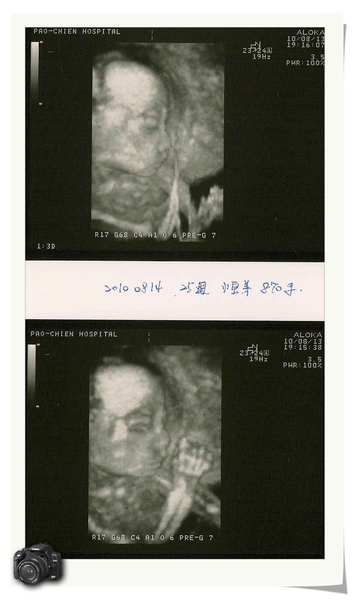

昨天是產檢的日子,小寶弟已經25周囉!現在870G,醫生說有比正常體重大一點,但是沒關係,總比體重輕好。昨天拍的是三D的,看的滿清楚的唷!

看的到小寶弟的側面跟小手唷! 小寶弟在摸自己的嘴嘴唷!leaf0817 發表在 痞客邦 留言(0) 人氣(29)